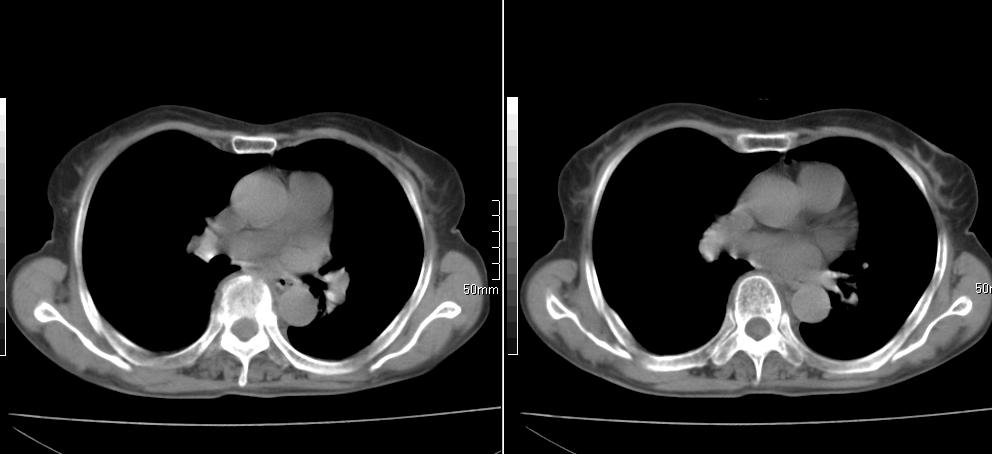

标题: CT26857:女,60岁,胃部不适前来就诊,不咳嗽,乏力,胸椎 [打印本页]

标题: CT26857:女,60岁,胃部不适前来就诊,不咳嗽,乏力,胸椎

1、胸椎有骨质破坏伴周软组织,考虑胸椎转移。2、考虑左肺上叶尖后段支气管开口区周围型肺癌可能。

1、胸椎有骨质破坏伴周软组织,考虑胸椎转移。2、考虑左肺上叶尖后段支气管开口区周围型肺癌可能。建议行纤支镜检查!

1、胸椎有骨质破坏伴周软组织,考虑胸椎转移。2、考虑左肺中央型肺癌可能。

椎体有高密度影,多系转移。

支持中央型肺癌,胸椎转移。

1)考虑左肺中央型肺癌。2)胸椎转移瘤不排除;建议行mri检查。